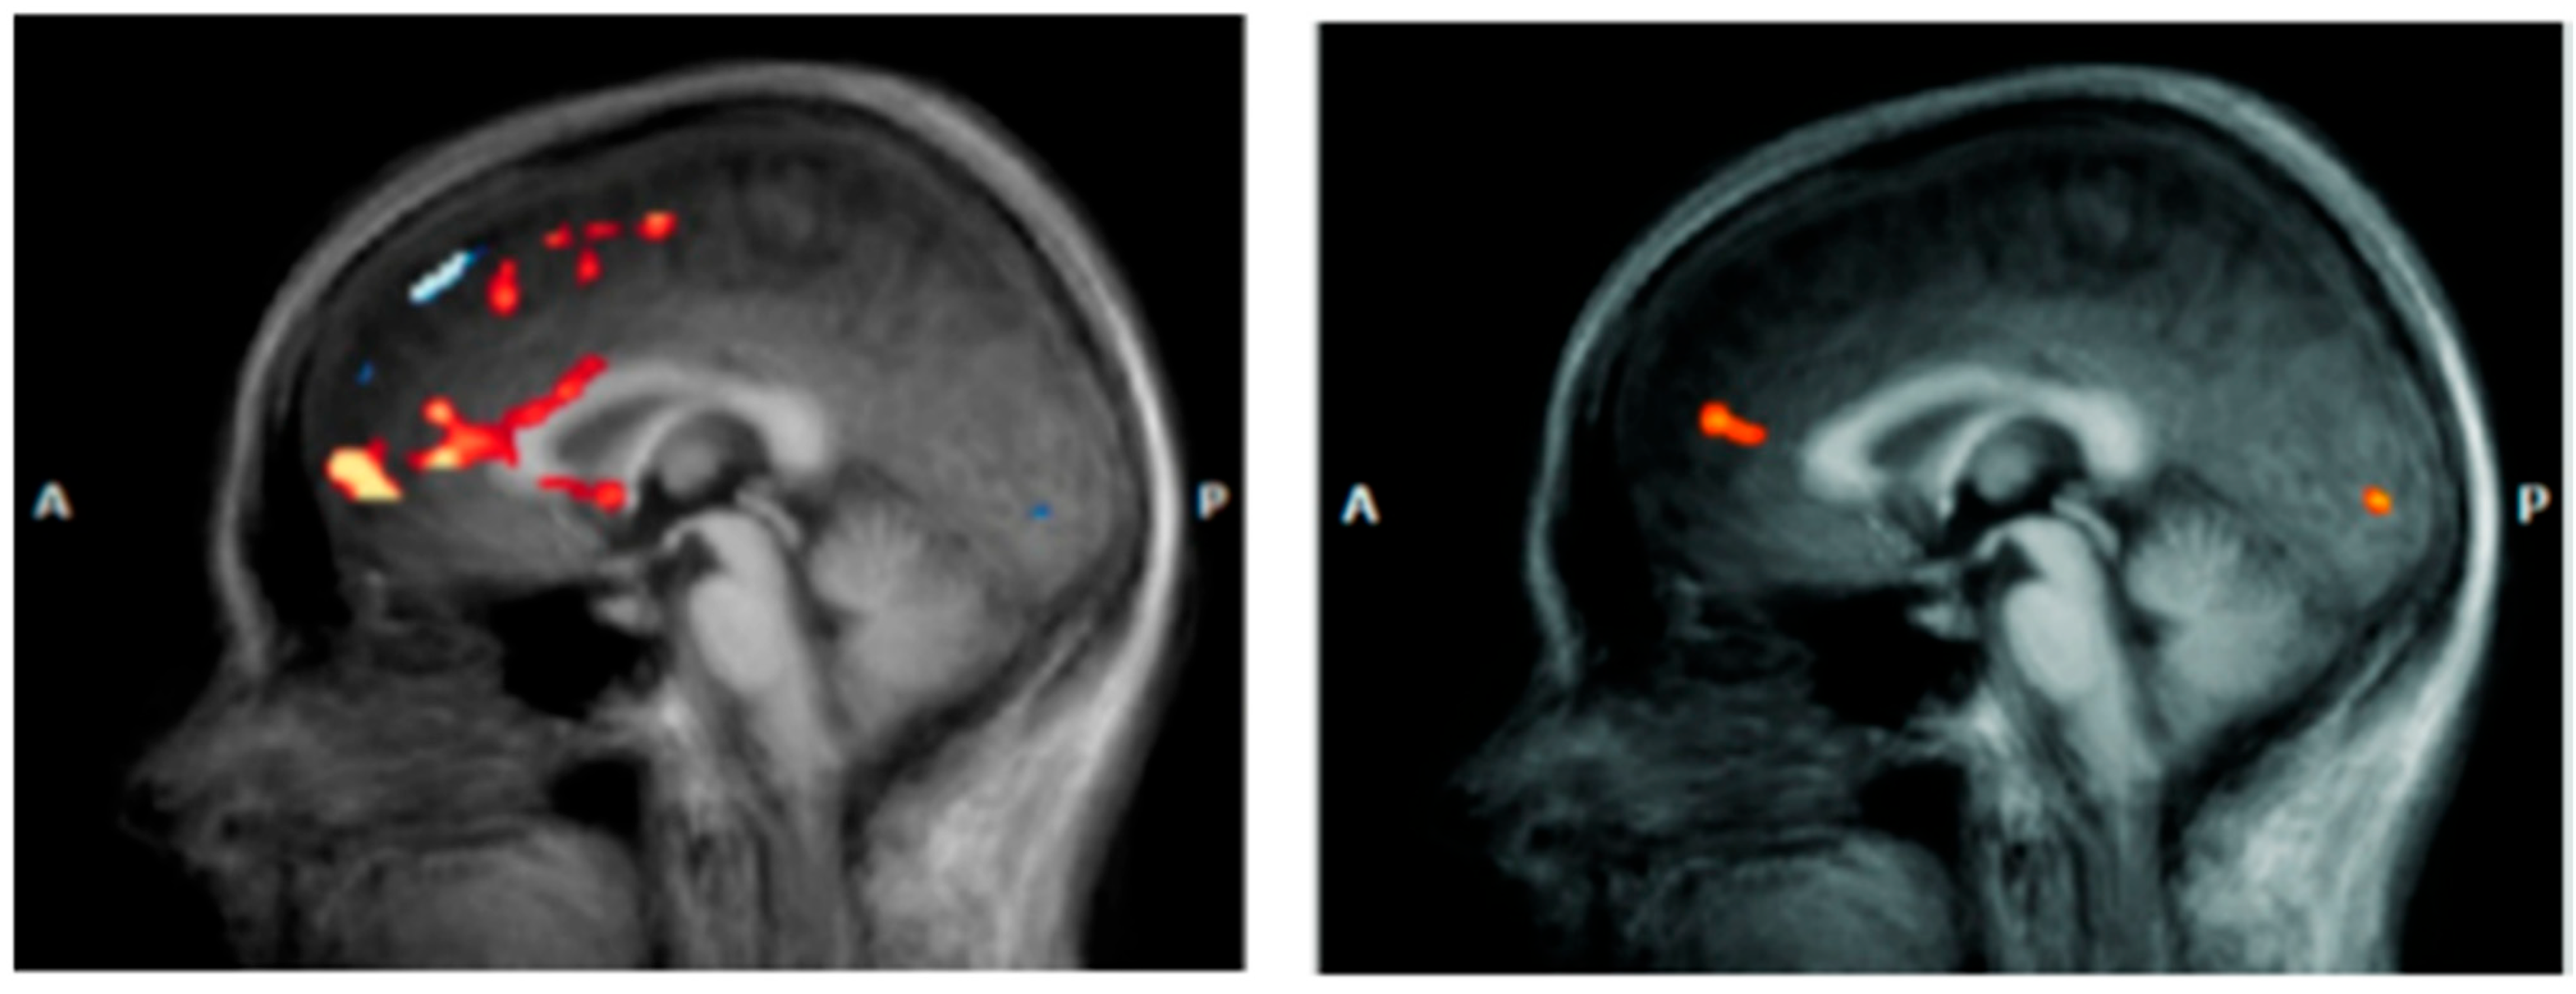

Amygdala. The amygdala serves as a crucial neural hub in depressive pathophysiology, representing the primary centre for negative emotion processing and threat response coordination [62]. Functional alterations of this structure result in pathological amplification of negative emotional responses while compromising fear extinction mechanisms, significantly contributing to the emotional dysregulation characteristic of DS. Neuroimaging studies consistently document amygdala hyperactivation patterns in response to negative emotional stimuli, with BOLD activity increases of 40–60% compared to healthy controls [63]. This hyperresponsivity shows selective characteristics, being particularly pronounced for negatively valenced stimuli while paradoxically reduced for positive stimuli, suggesting specific dysregulation of emotional processing circuits rather than generalized emotional reactivity (Figure 3). The basolateral amygdala demonstrates specific alterations in synaptic plasticity, with reduced GABAergic inhibition effectiveness leading to increased neuronal excitability [64]. High-resolution magnetic resonance studies have revealed microstructural modifications, including 12–18% increases in cellular density that correlate with symptom severity [65]. Connectivity between the amygdala and VMPFC shows significant compromise in DS, with 30–45% reductions in functional synchronization during emotional regulation tasks [66]. This disconnection compromises prefrontal top-down modulation effectiveness, perpetuating amygdala hyperactivation and limiting cognitive emotional control capacity. Diffusion tensor imaging studies have identified corresponding white matter alterations in tracts connecting the amygdala to the orbitofrontal cortex, with 15–25% reductions in fractional anisotropy correlating with depressive symptom intensity [67].

Figure 3.

Significant differences in amygdala–prefrontal cortex (PFC) functional connectivity (FC) among the major depressive disorder (DS) with a history of suicide attempts (SA), DS without a history of SA, and HC groups. Significant at p < 0.001, corrected by Gaussian random field (GRF) correction [68].